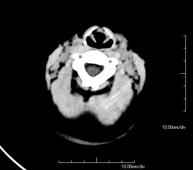

- TC Crani

Prova radiològica que consisteix en obtenir imatges del crani d'alta definició anatòmica (tronc cerebral, cerebel, cervell, calota cranial, etc. ) mitjançant l'ús d'un equip de TC (Tomografia Computeritzada). Indicacions: traumatismes, cefalea, trastorns de la memòria, pèrdua de força sobtada en una extremitat o meitat del cos. - TC Coll

- TC de crani

Prova radiològica que consisteix en obtenir imatges del crani d'alta definició anatòmica, mitjançant l'ús d'un equip de TC (Tomografia Computeritzada). Indicacions: cefalea, estudi de tumors, traumatisme cranial. - TC de coll